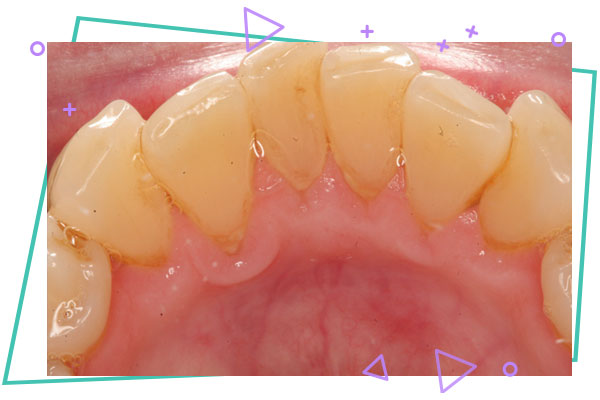

جرمگیری و تمیزکردن دندان

جرمگیری و تمیزکردن دندان : جرم دندان لایه ای زرد و سفت از میکروب ها و مواد غذایی است که به مرور زمان روی دندان